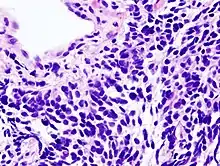

ما يقرب من 40٪ من حالات سرطان الرئة من النوع الغدي، التي تنشأ عادة في أنسجة الرئة المحيطية وترتبط معظم حالاتها بالتدخين. سرطان الرئة الغدي هو الشكل الأكثر شيوعاً من سرطان الرئة. نوع فرعي من غدية، bronchioloalveolar، هو أكثر شيوعاً في الإناث المدخنات وربما الاستجابات مختلفة للعلاج.

يشكل سرطان حرشفي الخلايا حوالي 30٪ من سرطانات الرئة. تشير الدراسات إلى أنها عادة ما تحدث بالقرب من الشعب الهوائية الرئيسية. عادة ما يتم العثور على تجاويف في منتصف الأورام الكبيرة بعد موت الخلايا فيها.

سرطان الخلايا الصغيرة يشكل نوع آخر من سرطان الرئة. يتفرد هذا النوع بإفراز عدد من الهرمونات مما يؤدي إلى متلازمة مصاحبة للورم.

حوالي 9٪ من سرطانات الرئة سرطان الخلايا الكبيرة. وسميت بهذا الاسم لأن هذه الخلايا السرطانية كبيرة، مع السيتوبلازم الزائدة، ونوى كبيرة الأنوية.